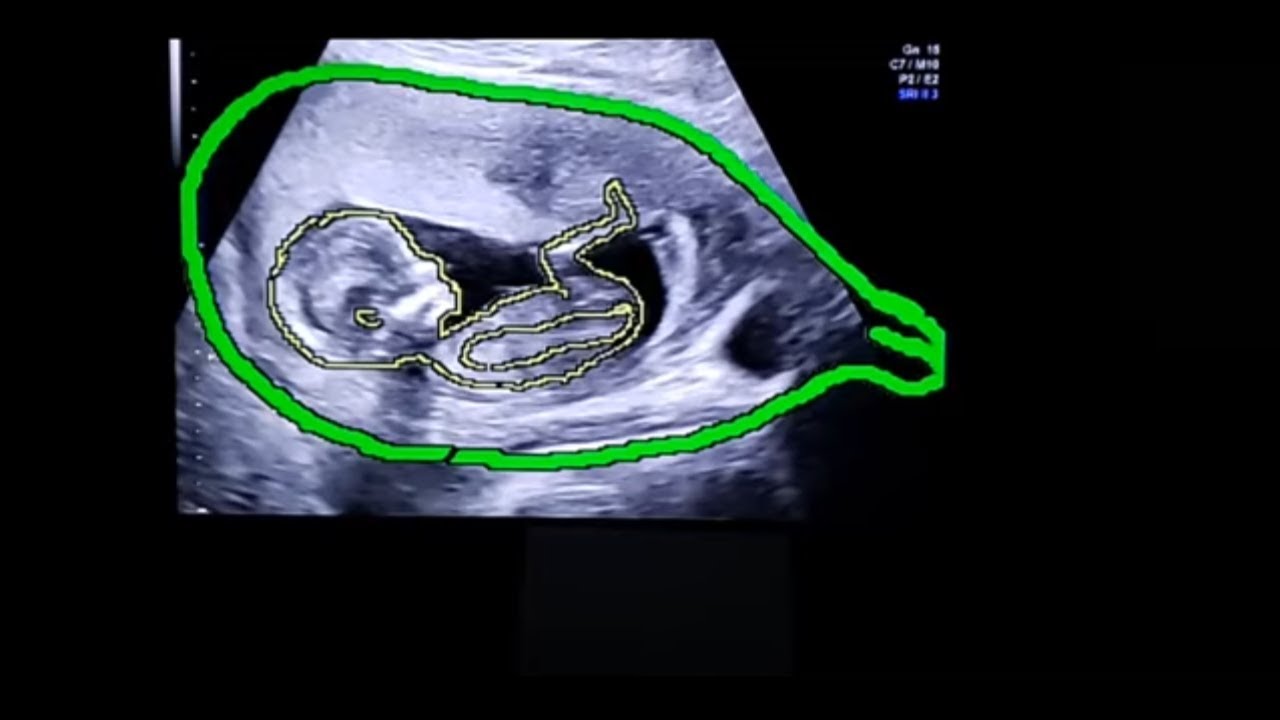

УЗИ Откровение: Узнаем пол ребенка в прямом эфире - Беременность 13 недель

В сегодняшнем видео Dr. Сильвио Омори раскрывает пол ребенка в прямом эфире с гестационным возрастом 13 недель. Во время этого акушерского УЗИ он разговаривает с матерью и использует технику, позволяющую нарисовать контур плода на изображениях УЗИ, что позволяет лучше рассмотреть матку беременной женщины.